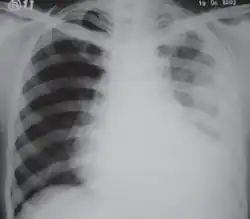

El diagnóstico del fibrotórax suele basarse en una historia clínica adecuada combinada con técnicas de imagen como la radiografía de tórax o la tomografía computarizada.[3] Estas herramientas detectan el engrosamiento pleural y la fibrosis alrededor de los pulmones.[7] La presencia de una corteza engrosada, con o sin calcificación, es una característica común en las imágenes.[3] Las tomografías computarizadas diferencian mejor si el engrosamiento se debe a depósitos de grasa o a fibrosis verdadera.[3]

En casos graves, el pulmón afectado puede perder volumen[7] y el mediastino puede desplazarse hacia el lado afectado.[3] Una reducción del tamaño de un lado del tórax en las imágenes sugiere cicatrización crónica.[6] Los signos de la enfermedad subyacente que causa el fibrotórax también se observan ocasionalmente en la radiografía.[6] Las pruebas de función pulmonar suelen mostrar hallazgos compatibles con una enfermedad pulmonar restrictiva.[6]